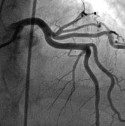

Herzkranke Diabetespatienten häufig falsch behandelt? Bypass-Operation sichert längere Überlebenszeit als Stent.

Diabetespatienten, die unter mehrfach verengten Herzkranzgefäßen leiden, sollten sich eher einer Bypass-Operation unterziehen als sich einen Stent legen zu lassen. Dies zeigt eine internationale Studie, die in der Fachzeitschrift „New England Journal of Medicine“ erschienen ist. An der Studie nahmen von 2005 bis 2010 insgesamt 1.900 Diabetespatienten aus 140 internationalen Behandlungszentren teil – darunter Kliniken aus den USA, Spanien, Kanada, Brasilien, Indien, Frankreich und Australien. Demnach überleben Diabetespatienten nach einer Bypass-OP deutlich länger als Diabetes-Patienten mit einer Gefäßstütze. „Beratung und Behandlung von herzkranken Menschen mit Diabetes müssen sich verbessern“, erklärt Professor Dr. med. Stephan Matthaei, Präsident der Deutschen Diabetes Gesellschaft (DDG). Es sei dringend erforderlich, dass Ärzte die Betroffenen vor einer Herzkatheteruntersuchung über den Überlebensvorteil der Bypass-Operation aufklären, fordert der DDG-Präsident.